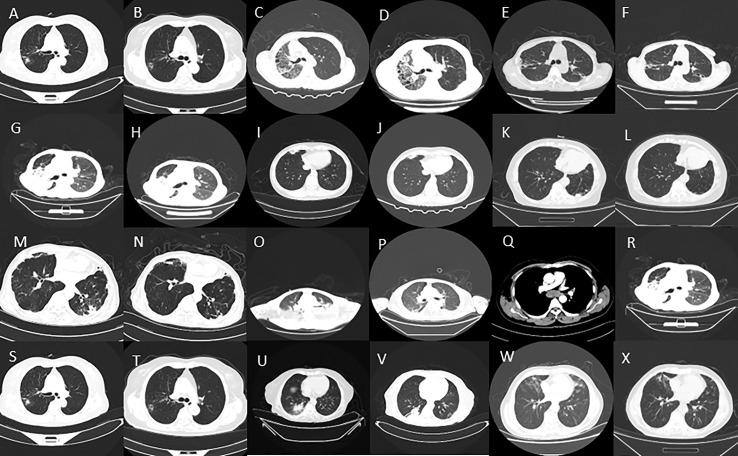

In this retrospective study, we enrolled 27 patients with NTM genomic sequences via mNGS and conducted a comprehensive clinical evaluation.

Pulmonary NTM disease was the most commonly observed presentation, with a subset of patients also presenting with extrapulmonary NTM infections.mNGS analysis identified six distinct NTM species, primarily Mycobacteriumavium complex (MAC), followed by Mycobacterium intracellulare andMycobacterium abscessus. Conventional routine culture methods encountered challenges, resulting in negative results for all available 22 samples. Among the 10 patients who underwent quantitative polymerase chain reaction (qPCR) testing, five tested positive for NTM.